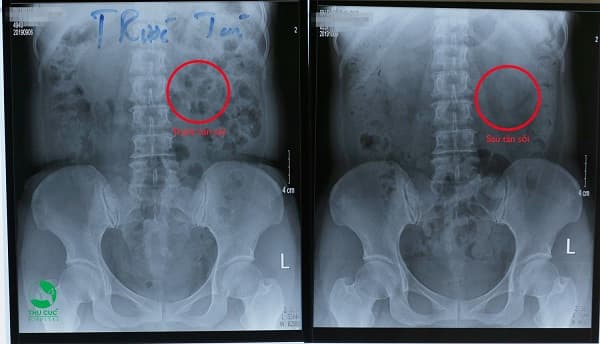

- Kết quả một ca tán sỏi ngoài cơ thể tại Bệnh viện ĐKQT Thu Cúc, sỏi đã sạch sau 1 lần tán.